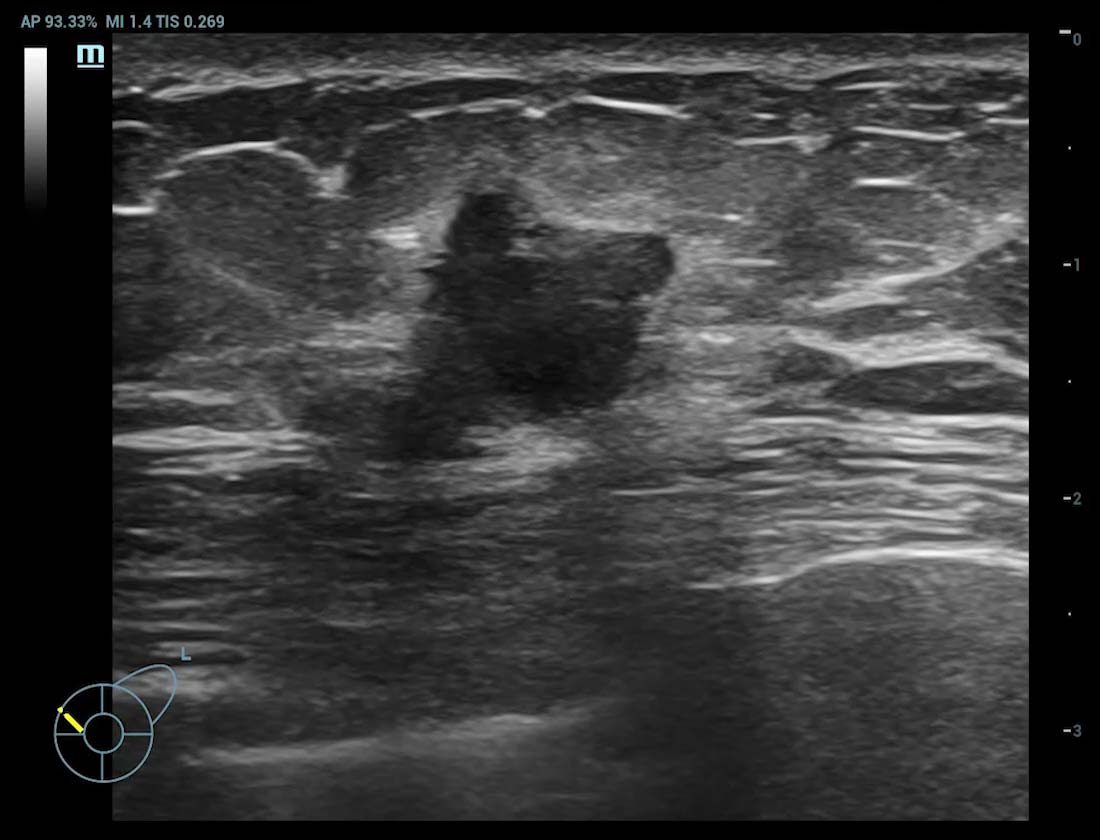

Smart Breast ã Tumor maligno

Smart Breast

O Smart Breast ûˋ uma ferramenta de anûÀlise e gera??o de relatû°rios de ultrassom mamûÀrio para tornar a rotina clûÙnica do ultrassom de mama mais precisa e produtiva. O gerenciamento sistemûÀtico de vûÀrias les?es e a avalia??o em quatro planos garantem ainda mais informa??es diagnû°sticas. Enquanto isso, o fluxo de trabalho automatizado simplificado aumenta a eficiûˆncia na varredura mamûÀria.

cUMA ã Massa mamûÀria

Massa mamûÀria